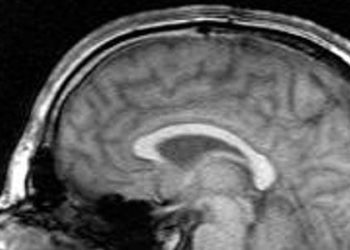

Study Rundown: Premature infants are at increased risk of cerebral palsy, a common childhood motor disorder associated with severe disability. Prenatal magnesium sulfate has become standard to protect fetal brains and lower cerebral palsy risk. However, there is no clear global consensus on when to administer it. The MAGENTA (Magnesium Sulfate at 30 to 34 Weeks’ Gestational Age) trial examined the impact of intravenous magnesium sulfate on pregnant individuals at risk of preterm birth between 30 to 34 weeks of gestation. The results showed no significant difference in death or cerebral palsy rates at 2 years between the magnesium and placebo groups. Interestingly, magnesium reduced respiratory distress syndrome and chronic lung disease in newborns but increased behavioral problems with an unknown biological basis. The study had limitations due to lower-than-expected events, which meant the sample size lacked the power to detect small differences between groups. These findings differ from earlier trials that found beneficial magnesium for reducing risk of cerebral palsy at earlier gestational ages but offer valuable insights for clinical decision-making surrounding the timing and necessity of prenatal magnesium sulfate administration.

In-Depth [randomized clinical trial]: This placebo-controlled randomized clinical trial involved 24 hospitals in Australia and New Zealand from January 2012 to April 2018. A total of 1433 pregnant individuals at risk of preterm birth and 1365 infants were enrolled in the study. Exclusion criteria included those with contraindications to magnesium sulfate (respiratory depression, hypotension, absent patellar reflexes, kidney failure or myasthenia gravis) and those who needed magnesium sulfate for treatment of preeclampsia. Participants were randomized to two groups, either receiving 4 g of magnesium or isotonic normal saline as placebo. The primary outcome was death (stillbirth, death before or after hospital discharge) or cerebral palsy in children at 2 years’ corrected age. At the follow-up, neurological, psychological and caregiver-reported assessments were also completed. There were 36 secondary outcomes that further assessed the health of the pregnant individual and infant. At 2 years, death or cerebral palsy was not statistically significant between groups, with an adjusted risk ratio of 1.19, p=0.57. Adverse events were 3.76 times more likely to occur in individuals who received magnesium versus placebo, but they tended to be minor infusion-related side effects and not life-threatening ones. Overall, the study conducted a thorough assessment of multiple health outcomes postnatally and contributed to the efficacy and safety profile of magnesium sulfate prenatally.